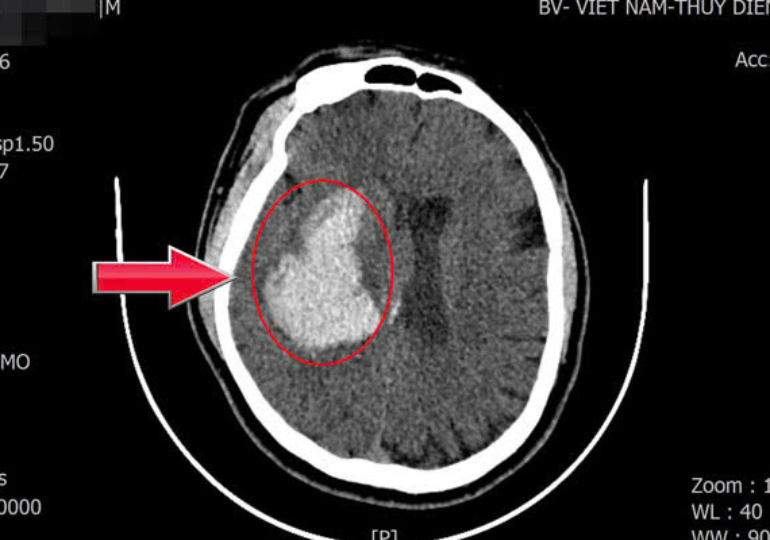

Người đàn ông đột quỵ sau khi uống 8 lon nước tăng lực mỗi ngày

Chữa đột quỵ sai cách: Chuyên gia cảnh báo thông tin sai lệch, có thể đánh đổi bằng tính mạng

5 điều cấm kỵ khi cứu người bị đột quỵ

Bật dậy quá nhanh sau khi ngủ dậy dễ gây đột quỵ não?

3 "thủ phạm" làm tăng nguy cơ đột quỵ, nên cẩn thận!

Trời rét, bệnh nhân đột quỵ gia tăng, nguyên nhân là gì?